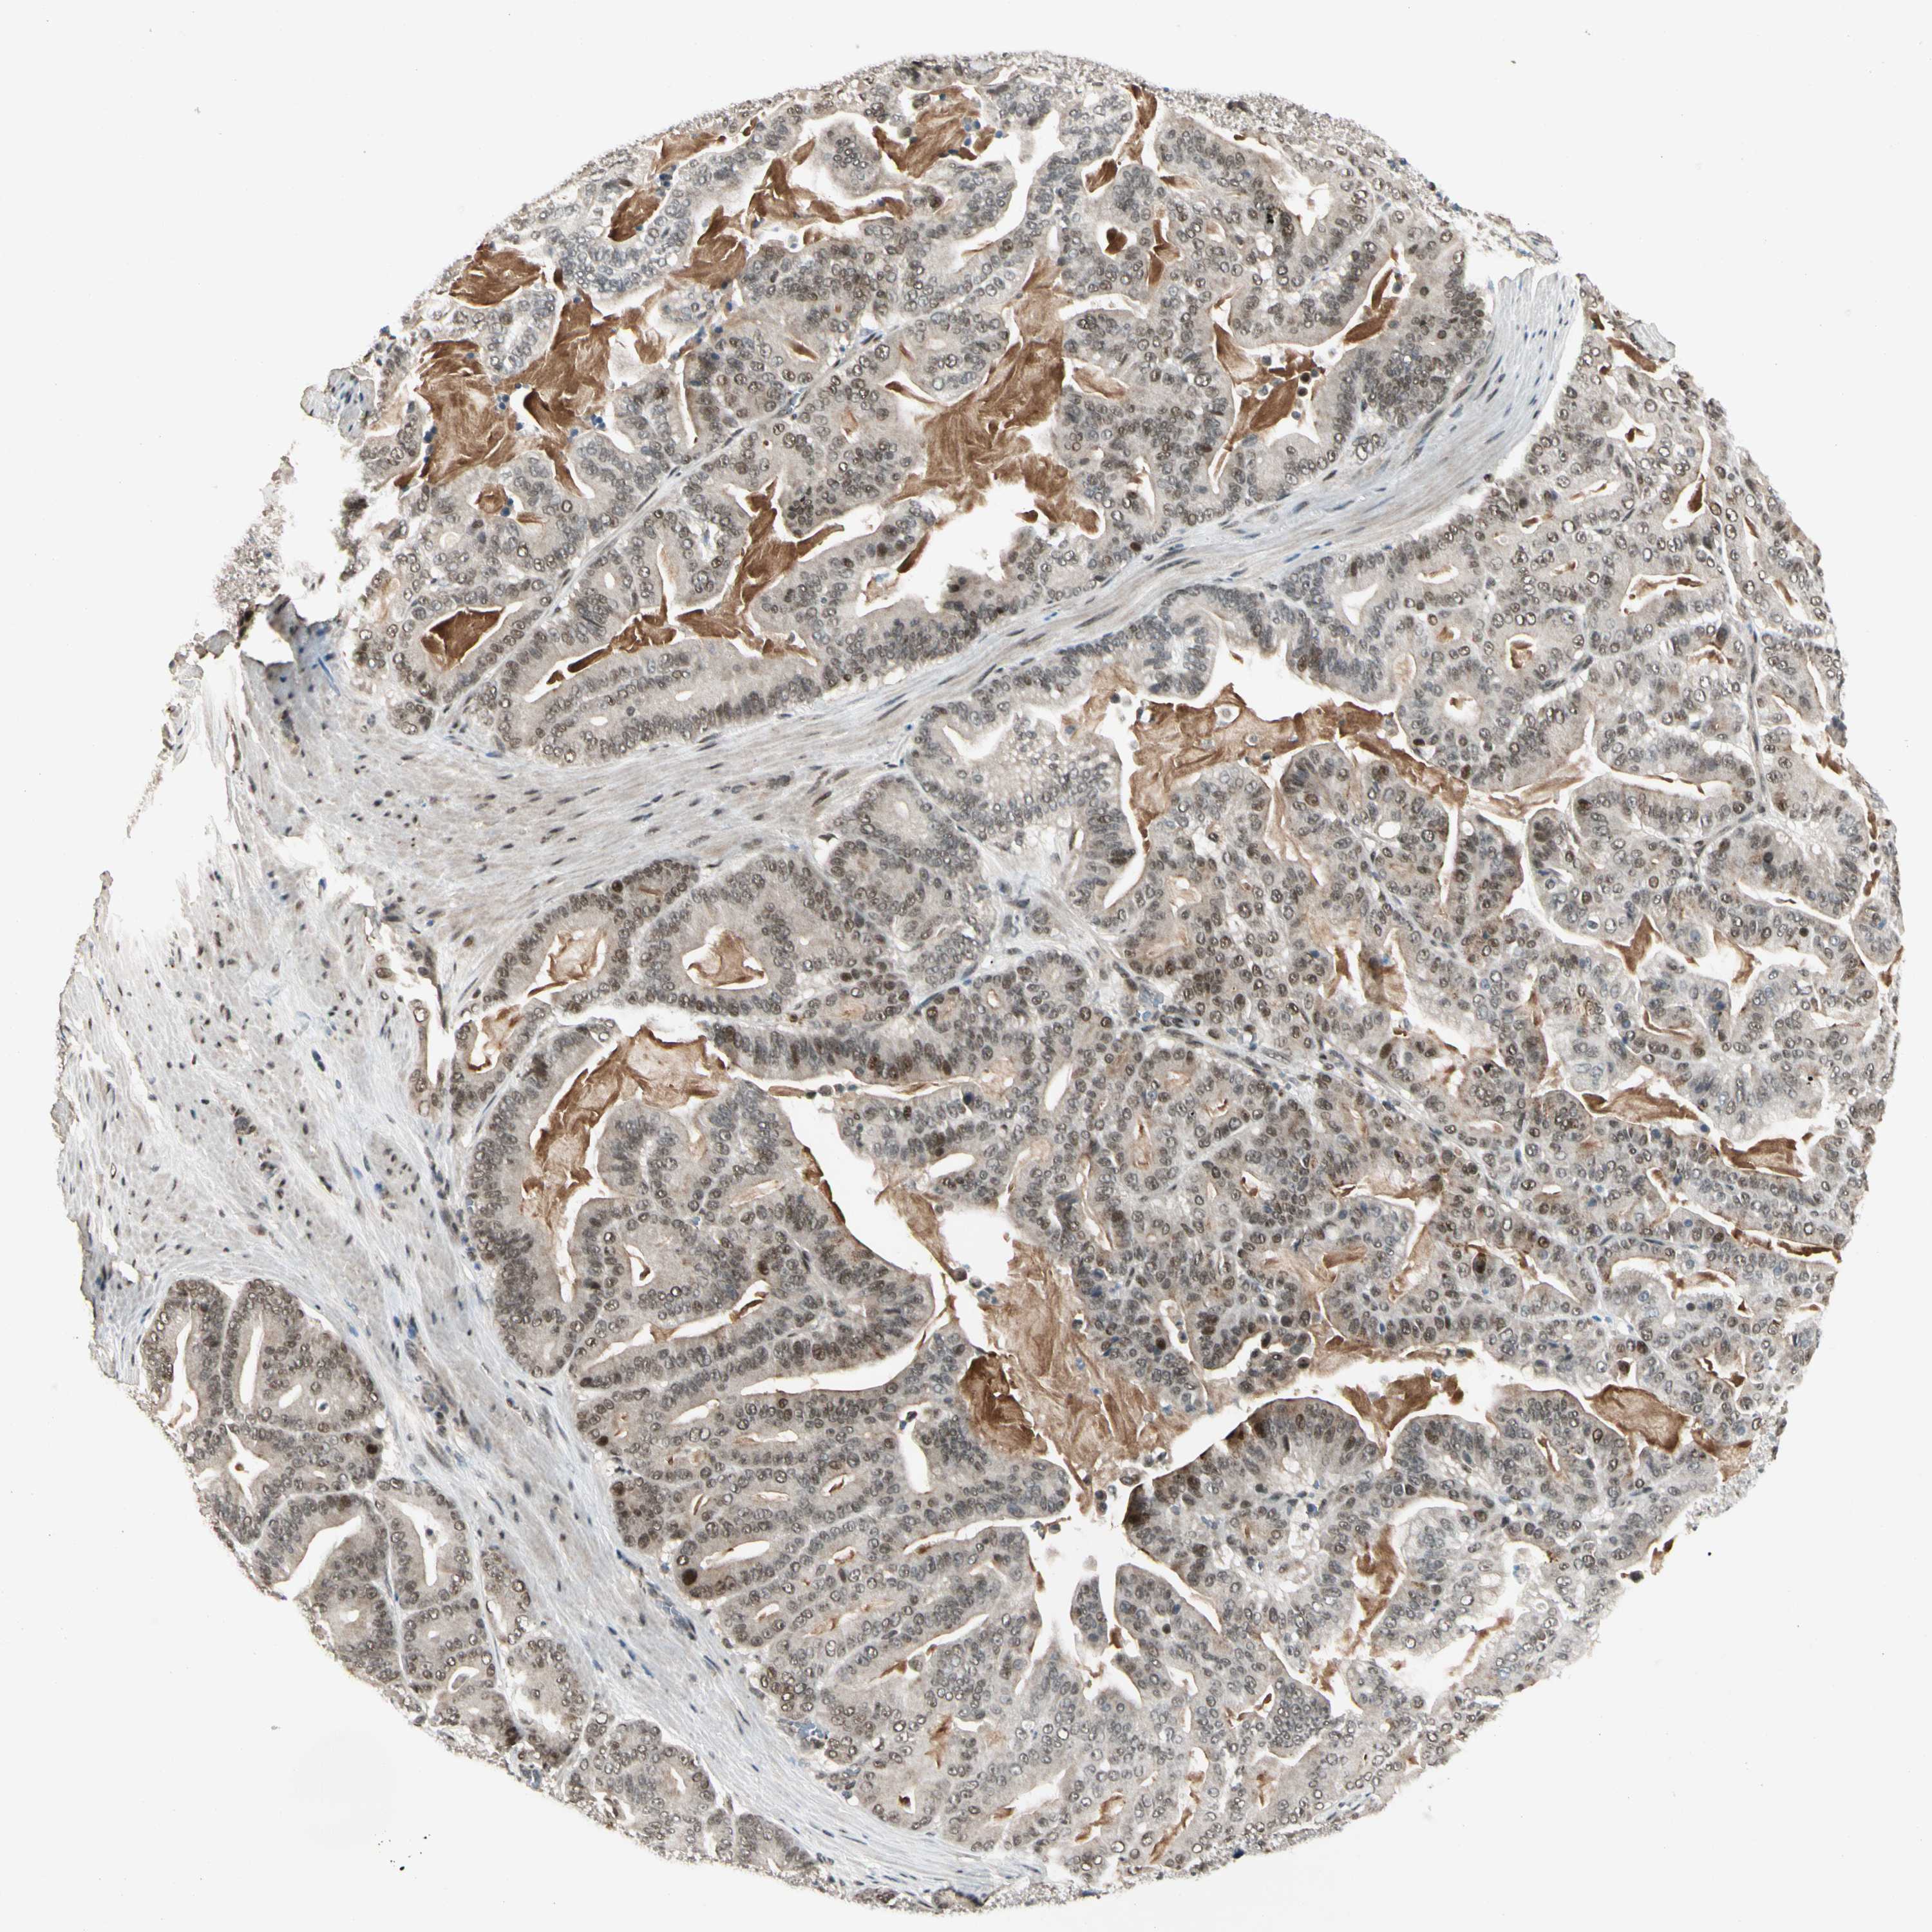

PANCREATIC CANCER - Protein expressioni

A mouse-over function shows sample information and annotation data. Click on an image to view it in a full screen mode. Samples can be filtered based on level of antibody staining by selecting one or several of the following categories: high, medium, low and not detected. The assay and annotation is described here.

Note that samples used for immunohistochemistry by the Human Protein Atlas do not correspond to samples in the TCGA dataset.

Antibody stainingi

Antibody staining in the annotated cell types in the current human tissue is reported as not detected, low, medium, or high, based on conventional immunohistochemistry profiling in selected tissues. This score is based on the combination of the staining intensity and fraction of stained cells.

Each image is clickable and will lead to virtual microscopy that enables deeper exploration of all samples and also displays staining intensity scores, fraction scores and subcellular localization as well as patient and tissue information for each sample.

Antibody HPA007990

Staining

High

Medium

Low

Not detected

Intensity

Strong

Moderate

Weak

Negative

Quantity

>75%

75%-25%

<25%

None

Location

Nuclear

Cytoplasmic/membranous

Cytoplasmic/membranous,nuclear

Adenocarcinoma, NOS